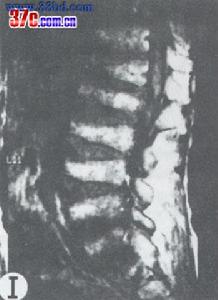

患者,男,10歲,全身關節痛5年余,近1年來,全身關節疼痛更顯著,活動後易疲勞。其家族無其他人患此病。查體:身高106cm,體重26kg,智力尚正常,步態不穩。“X”型腿,雙手粗而短,指間關節腫脹,雙肘、雙膝、雙踝粗大,無紅熱,脊柱後凸,四肢與軀幹基本均稱。實驗室檢查:無不良發現。X線表現:兩側骨骺對稱性受累,骨骺發育小及變扁,可見呈分節或斑點狀,邊緣不規則,但無硬化帶。雙手掌指骨短,乾骺端粗大,雙舟骨不規則狀變形,各腕骨間骨間隙變窄。脊柱各椎體稍變扁,上下緣不規則且毛糙,頸椎下各

椎間隙稍變窄,腰椎第3、4、5椎體前後徑小,且胸腰段以胸11椎體至腰1椎體為中心後凸畸形。骨盆變窄,呈狹長型改變,雙股骨頭骨骺變扁平,並見有分節及斑點狀改變,股骨頸變短,髖臼變淺,雙膝關節間隙外寬內窄,雙側脛骨遠端骨骺外側部分發育不良,較細小,骨骺呈尖端指向外側之楔形,雙踝關節面傾斜。

多發性骨骺發育不良多發性骨骺發育不良據資料於1921年首先被Barringten-Ward報導,1947年命名。本病僅侵犯骨骺軟骨,主要為軟骨發育過程中先期鈣化帶區的軟骨細胞未成熟,數量減少、排列不規整,致骨化障礙。本病男女均可發病,約50%系家族性發病。一般於4歲以後出現症狀,表現為關節疼痛,運動障礙和步態不穩。病變只侵犯及骨骺,以兒童時期最顯著,尤其以11-12歲症狀最明顯,青春期後隨年齡增長症狀可改善。身材較短小,四肢與軀幹基本勻稱,手足可粗短。表現為骨骺發育小而且變扁,邊緣不規則,可呈分節或斑點狀,但無硬化。管狀骨變短,關節面傾斜,脊柱後凸畸形,脛骨遠端骨骺有特徵性表現。隨年齡增長而乾骺端變小、扁平及關節畸形,較早地引起退行性骨關節病。本病須與軟骨發育不全、乾骺發育不良等骨關節發育障礙相鑑別。如能結合病史及其特徵性X線表現,是不難鑑別的。